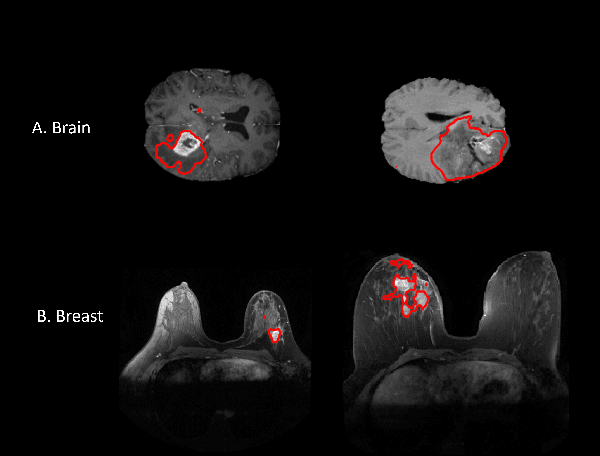

Figure 1 for Cross-Domain Federated Learning in Medical Imaging